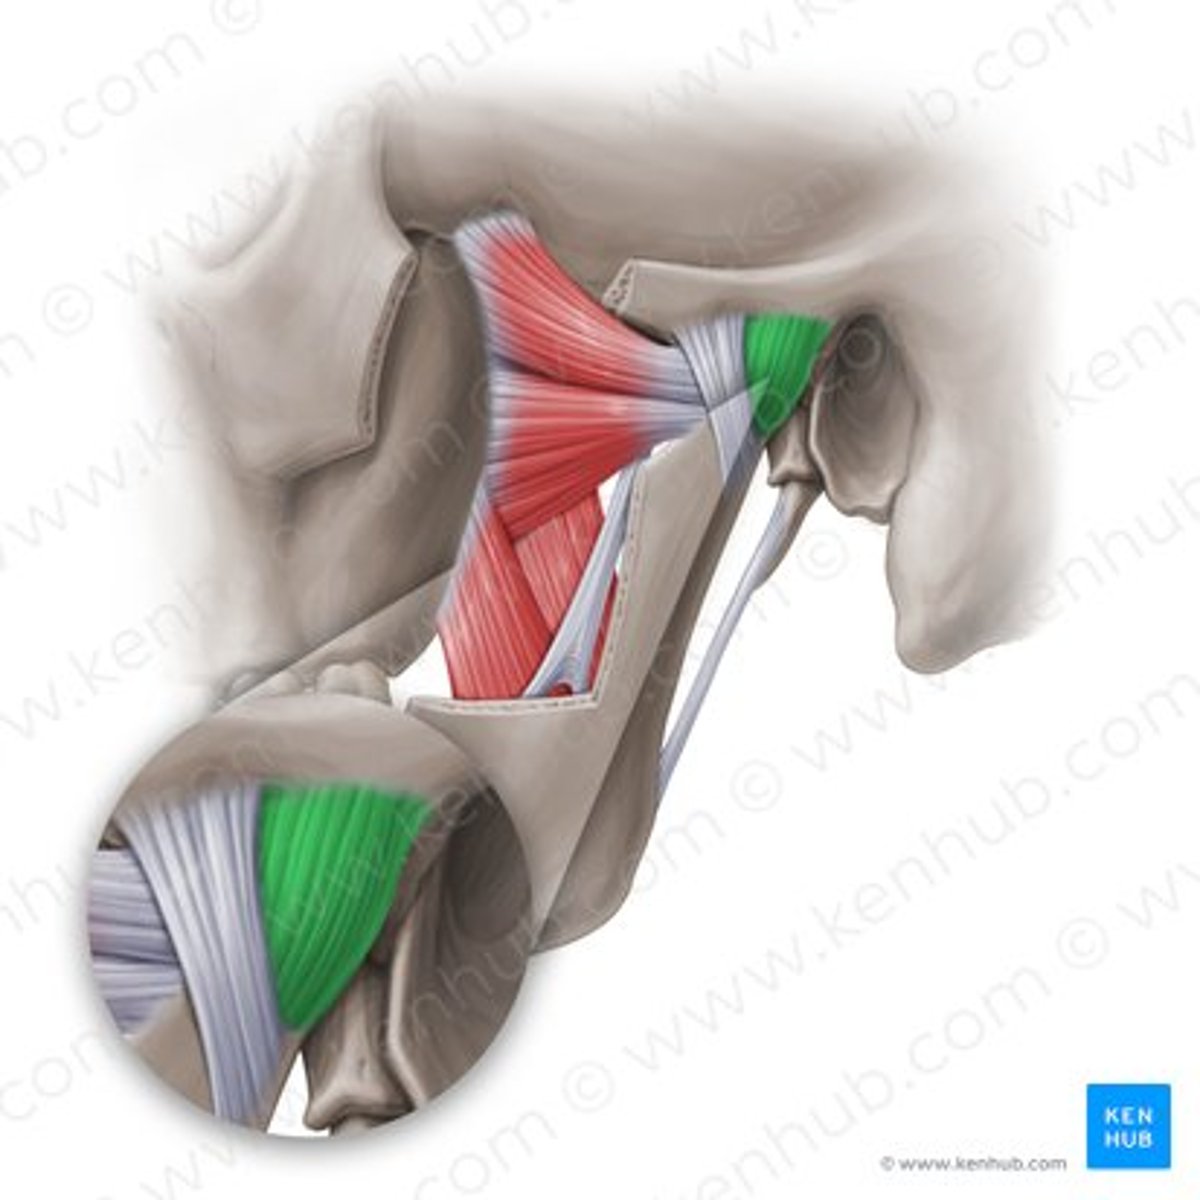

deep masseter

superficial masseter

temporalis

lateral pterygoid

lateral pterygoid, superior part

lateral pterygoid, inferior part